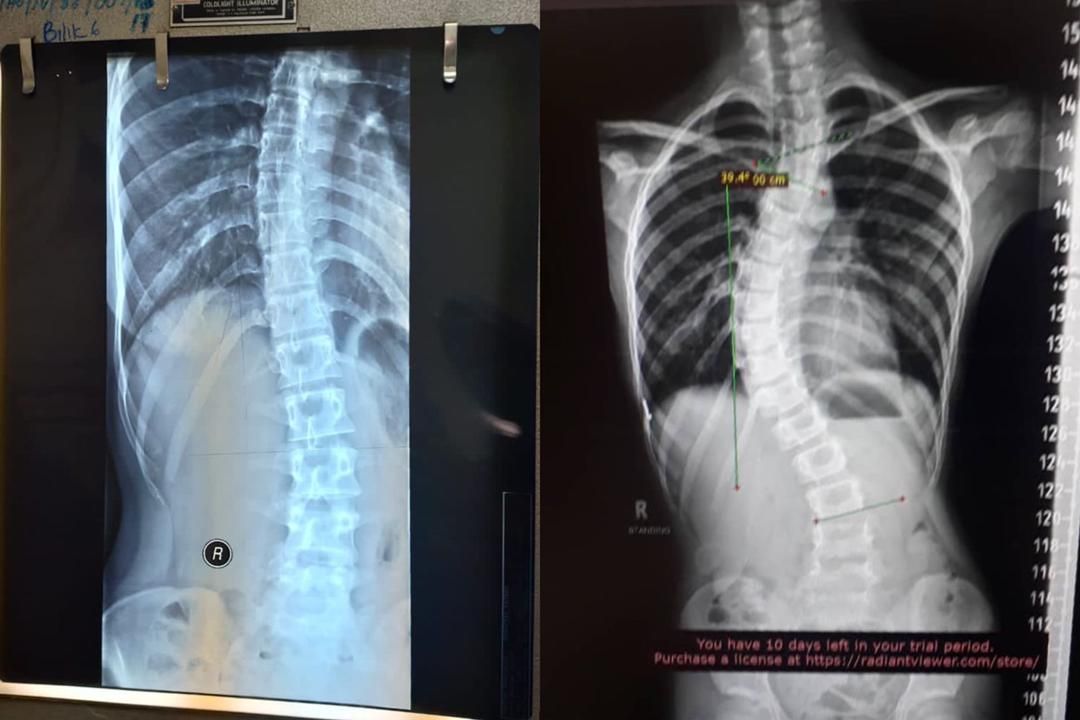

21岁的努琳阿蒂里阿娜阿丽法与“mStar”分享了她的故事。她说,2019年她还在上学时,发现自己患有脊柱侧弯。

“我第一次发现脊柱侧弯是在我18岁的时候,当时我经常感到脖子无力,还认为这可能是有一次骑摩托车去朋友家时发生车祸的结果,但显然不是。

“当我感觉越来越不舒服时,立即告诉父母请他们带我到附近的诊所检查。医生检查过后,建议我到加影医院再做一次X光检查。

“照了X光后,我才知道脊椎弯曲了,它并非意外造成,因为在意外发生前我就有腰痛,我还以为腰痛是正常的,因为我时常有帮忙做家务,又或者是来月经时造成的。”

“当我们带妹妹到加影医院检查时,医生告知说她也患有脊柱侧弯,且情况比我的更糟,因为她的骨头弯曲的巴仙率更高。